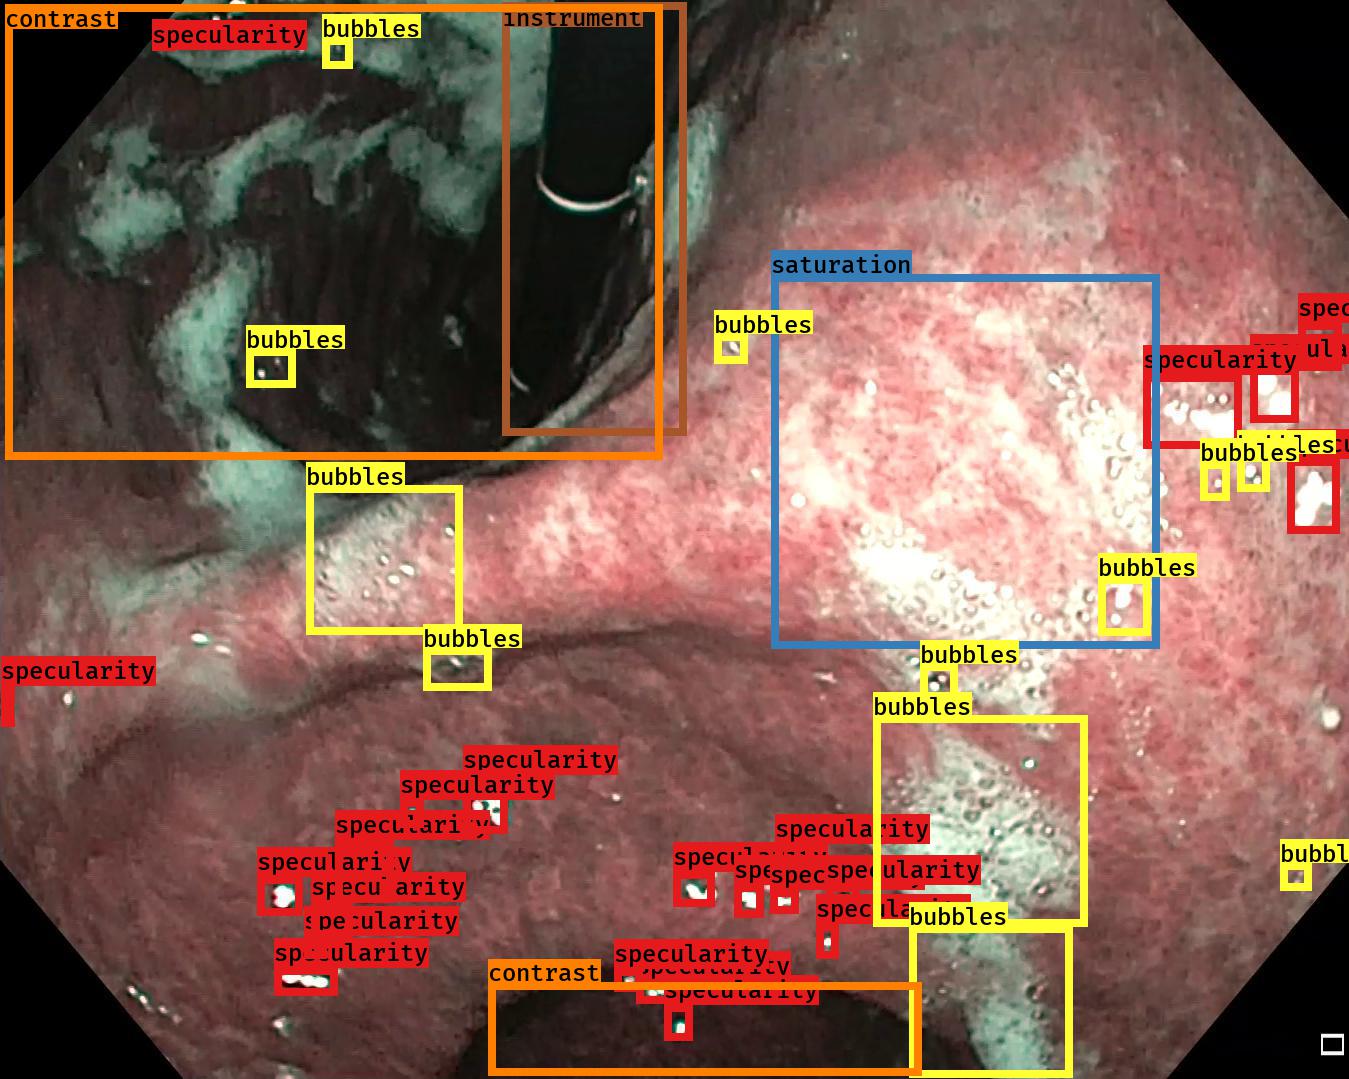

Examples for bounding box annotations for detection are shown in Fig. 2. It can be observed that while multiple boxes are annotated for several small specular areas; contrast, blur and instrument have relatively larger areas. Due to the overlap between two or more classes, the annotation by experts varied. This was minimized by following the detailed annotation protocol above. For semantic segmentation, a larger area mask was preferentially used to delineate locally very cluttered small specularity artifacts (see Fig. 3).